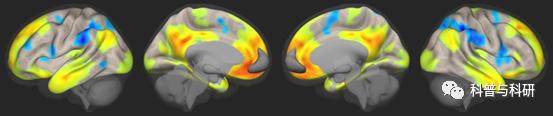

常用静息态功能指标介绍及SPM统计(理论+实操) |

1、静息态功能磁共振分析方法概论 2、静息态功能磁共振分析方法预处理(时间矫正、头动矫正、标准化、平滑等) 3、静息态数据预处理的批处理过程讲解 4、图像计算小工具介绍 5、ReHo、ALFF、fALFF、DC、PerAF、FC等指标计算 6、单样本t、双样本t、配对t检验 7、作图可视化 |

静息态指标计算 基于SPM统计 多重比较校正 |

1、ReHo、ALFF、fALFF、DC、FCD、FC、PerAF等指标介绍及实操 2、单样本t、双样本t检验 3、多重比较矫正(FWE,FDR,GRF,AlphaSim) |

基于灰质功能指标计算 |

1、ReHo、ALFF、fALFF、DC、FCD、FC、PerAF等指标介绍及实操 2、单样本t、双样本t检验 3、多重比较矫正(FWE,FDR,GRF,AlphaSim) |

静息态常规指标分析

(1)局部脑区和基于体素的Reho、alff、falff Voxel-FC 、Dc、FCD分析